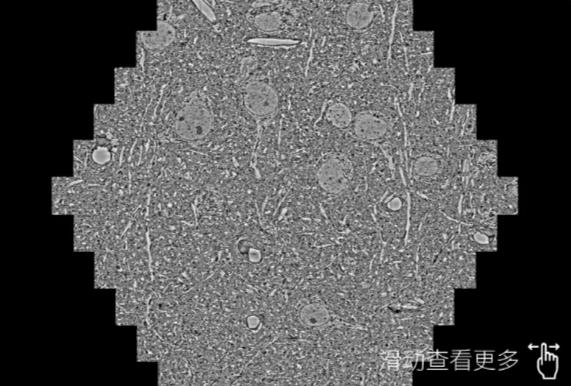

鼠脑切片。左图使用朝阳蔡司朝阳扫描电镜MultiSEM706对165μmx143pm面积区域成像,耗时仅需1.5秒。右图为鼠脑切片中30μm区域放大效果。样品由芝加哥大学B.Kasthuri提供。